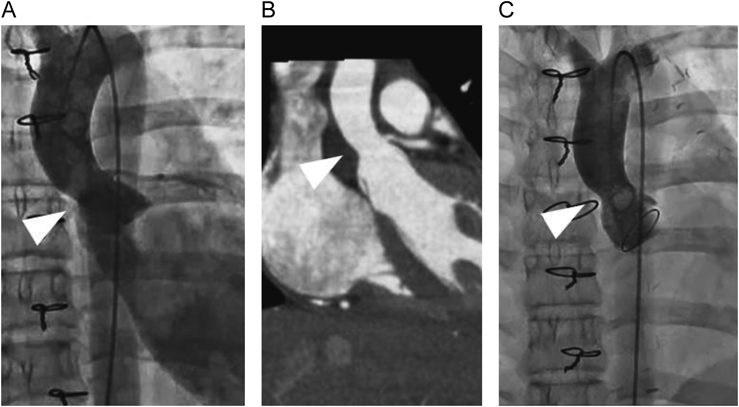

A 12-year-old girl with an anomalous origin of the left coronary artery from the right coronary cusp, characterized by intramural course of the coronary artery, underwent unroofing of the left main trunk. During the surgical procedure, aortic regurgitation (AR) emerged, prompting us to attempt commissural suspension and plasty to the right coronary cusp. Despite the aortic valve intervention included within a total cardiac arrest duration of 174 minutes, a trivial-mild degree of AR persisted. Subsequently, AR through the central and commissural regions between the left and the right coronary cusps progressively deteriorated (Fig. 1). The left ventricular end-diastolic diameter increased from 42 mm to 45 mm over a period of six months. Cardiac catheterization performed three months postoperatively revealed left ventricular end-diastolic pressure of 16 mmHg, AR being categorized as Sellers IV. Despite the absence of a discernible pressure gradient, morphological constriction was noted at the sino-tubular junction (Fig. 2A). Additionally, contrast-enhanced computed tomography confirmed the narrowing of the sino-tubular junction (Fig. 2B). Given the patient’s age and activity level, we considered AVNeo as a viable alternative to mechanical valve replacement.

Fig. 2 (A) Preoperative cardiac catheterization image. (B) Preoperative contrast enhanced computed tomography image. (C) Postoperative cardiac catheterization image. The white arrow heads denote the sino-tubular junction.

Following dissection around the heart, the pericardium was harvested and subjected to glutaraldehyde treatment for seven minutes. After induction of cardioplegic arrest, a transverse aortotomy was performed in the proximal ascending aorta, approximately 1.5 cm distal to the right coronary ostium. All three leaflets exhibited thickening, particularly the left coronary cusp, necessitating complete resection. The dimension of the non-coronary cusp was measured 17 mm, and 15 mm each for the right and the left coronary cusps. Three new aortic valve leaflets were meticulously fashioned from the glutaraldehyde-treated autologous pericardium using a commercially available template. Subsequently, these were sutured to the remnant hinges of the resected leaflets and the aortic wall (Fig. 3). The aortotomy was reinforced with a patch of the glutaraldehyde-treated autologous pericardium. During the weaning process from cardiopulmonary bypass, ventricular fibrillation occurred frequently. Direct pressure measurements indicated that left atrial pressure exceeded 30 mmHg, while transesophageal echocardiography revealed diminished left ventricular contractility. The peak flow velocity across the aortic valve was measured as 4.1 m/s. Consequently, cardiac arrest was induced again; the previous aortotomy was extended into the non-coronary sinus, the reconstructed leaflets were all excised, and a 17 mm St. Jude Medical Regent valve (St. Jude Medical, St. Paul, MN) was positioned in the supra-annular location following aortic annular enlargement by the Nicks procedure. Subsequent to this revision, weaning from cardiopulmonary bypass was successfully achieved, and an estimated pressure gradient across the aortic valve became less than 20 mmHg. (The first aortic cross-clamp time was 186 minutes, and the second 143 minutes.) After a prolonged 10-day intensive care unit stay due to persistent pleural effusion, the patient was discharged home on the postoperative day 25.

At the four-month postoperative assessment, cardiac catheterization revealed morphological constriction of the sino-tubular junction (Fig. 2C). On the other hand, trans-thoracic echocardiography did not indicate aortic stenosis; a peak velocity (Vmax) of 0.8 m/s and a mean pressure gradient (PG) of 2 mmHg.